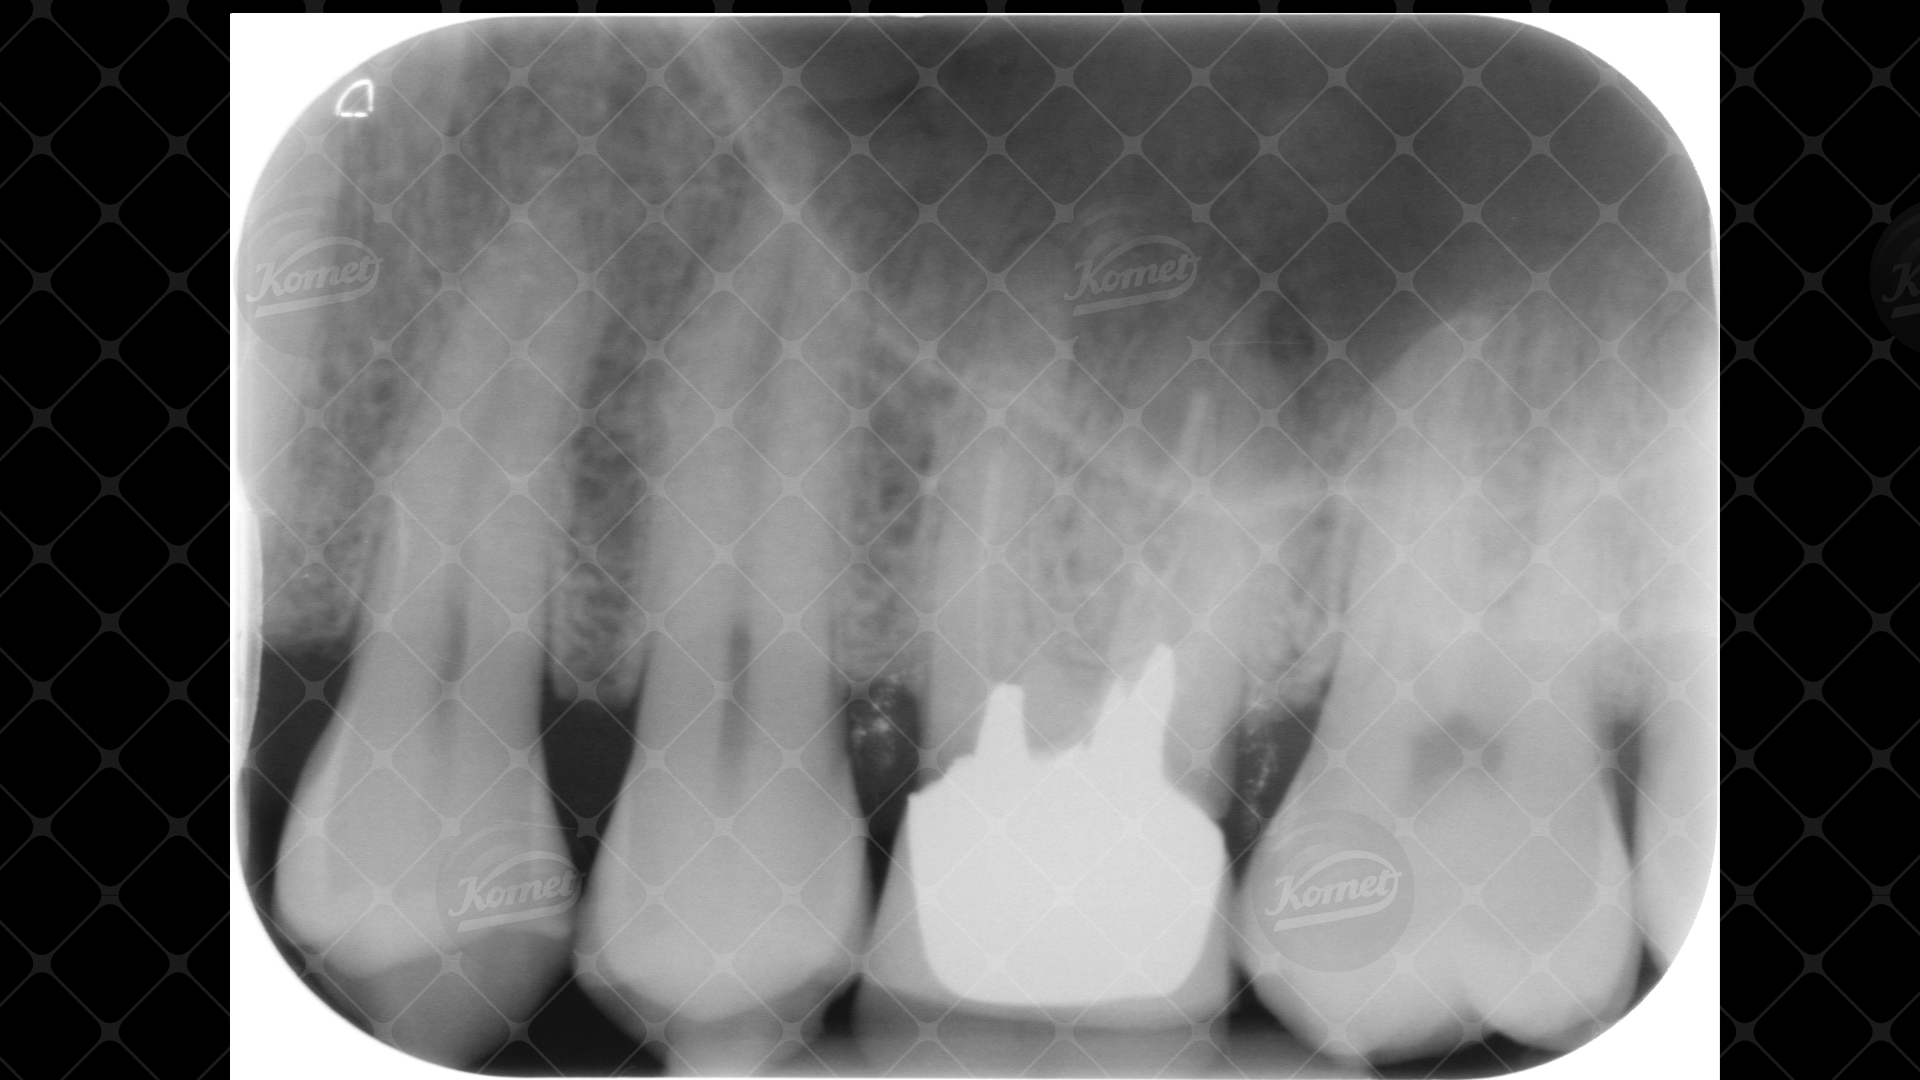

Il paziente si presenta in studio per la decementazione del manufatto protesico sul 26 e si decide pertanto di procedere al ritrattamento endodontico prima di protesizzare di nuovo il dente. Il perno metallico fuso viene rimosso dopo essere stato separato; grazie gli inserti sonici SF-66 e SF-68 si ridefinisce la nuova cavità d’accesso al sistema canalare, rimuovendo possibili fattori confondenti come cementi o materiale organico. In particolare grazie all’utilizzo della fresa H1SML31.205.006 a gambo lungo (31mm) si esplora il pavimento della camera pulpare alla ricerca della possibile presenza di un secondo canale nella radice MV. In seguito a questa operazione si reperiscono addirittura 3 imbocchi supplementari (due di questi confluiscono in un unico canale): una volta sagomato e deterso adeguatamente il sistema canalare si possono così distinguere un canale MV (sagomato con F6 Skytaper 030), un MV2 (confluente con il precedente sagomato con F6 Skytaper 025), un MV3 (F6 Skytaper 025), un DV (F6 Skytaper 030) e un P (F360 045). I canali P, DV, MV e MV2 vengono poi sigillati con guttaperca in abbinamento ad un cemento bioceramico; con sistema di guttaperca veicolata da carrier per quanto riguarda MV3.

Si è successivamente provveduto a ricostruire il dente, non prima di aver eseguito una carie sulla parete mesiale del 27, sfruttando il favorevole accesso e quindi la possibilità di maggiore conservazione di struttura dentale sana. La ricostruzione del pilastro protesico è avvenuta invece preparando il post space a carico della radice P e posizionando nella medesima un Dentin Post Coated 110: il perno in fibra è stato come sempre cementato con cemento duale dopo aver ricostruito perifericamente il dente.